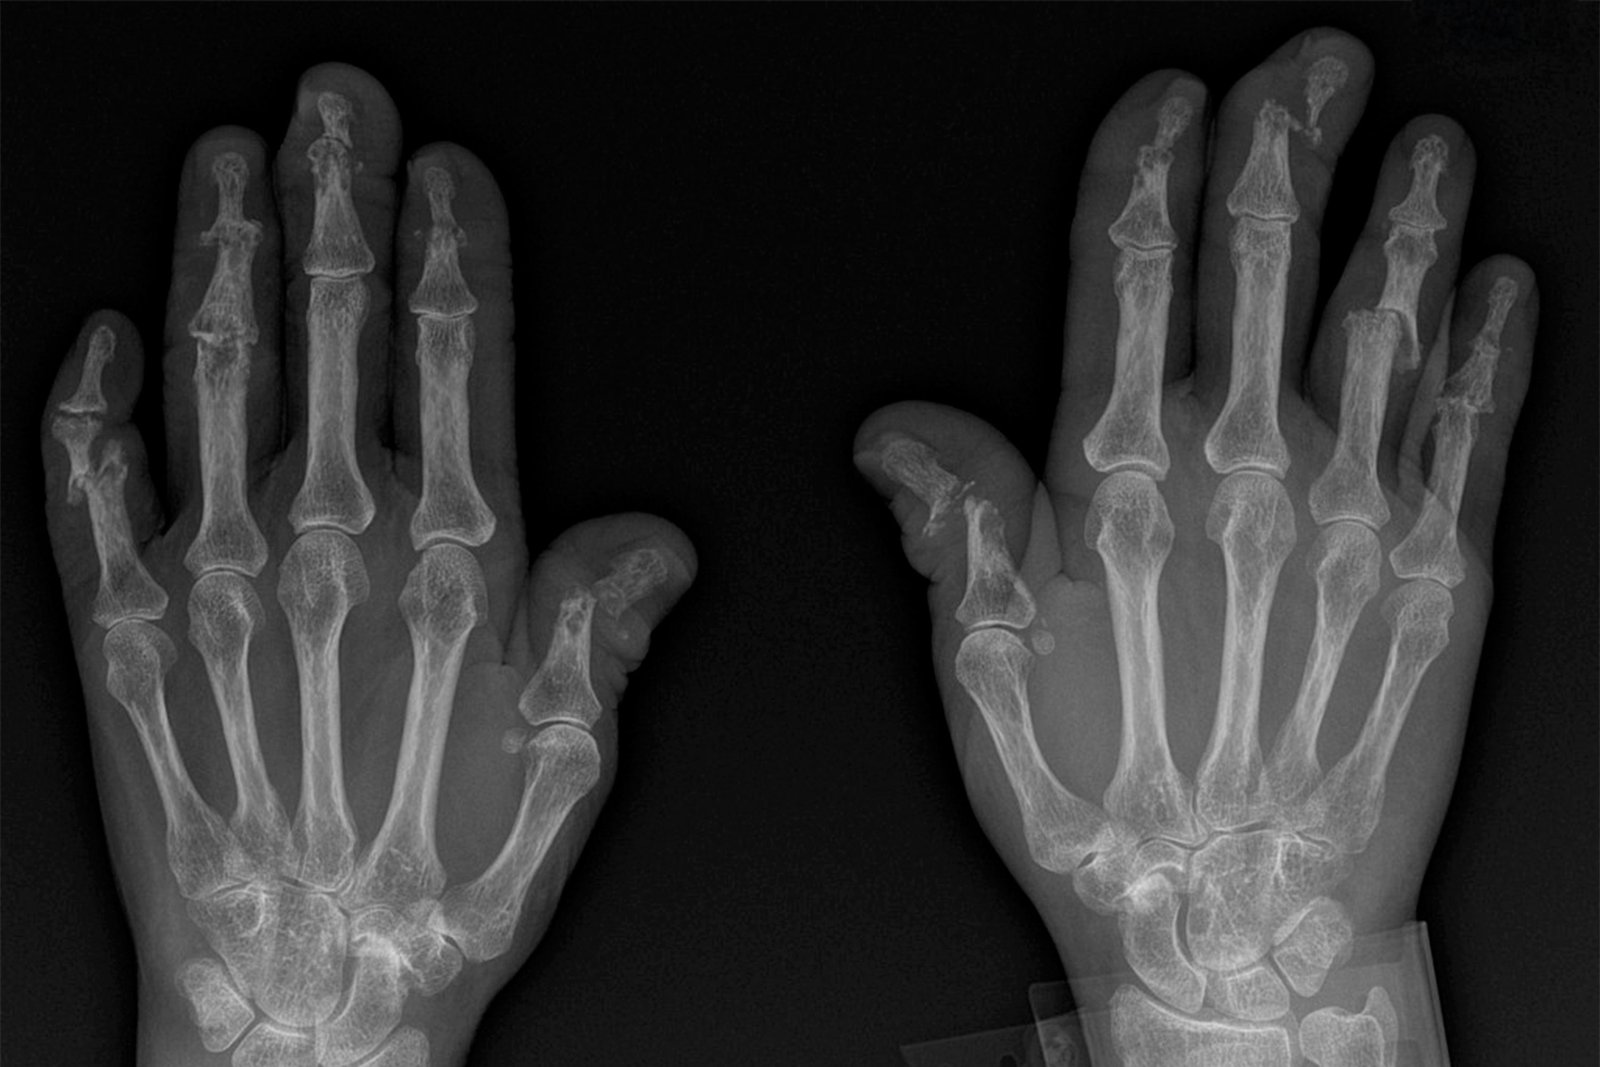

• 1. Arthritis is swelling and pain at one or more joints.

• 2. At SOH we provide comprehensive management of arthritis which includes

• 3. Early diagnosis of different types of arthritis.

• 4. Optimal medical management.

• 5. Prevention of pain and joint deformity and maintaining joint mobility by effective physiotherapy.

• 6. Surgical intervention in end stage disease in form of arthrodesis or joint replacement.